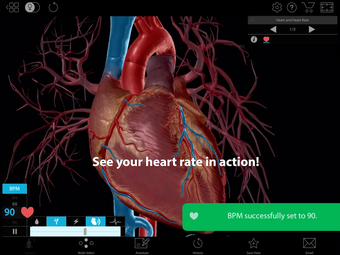

One of the most remarkable features of this application is that it enables users to compare 3D models of normal anatomy with models of common diseases and conditions. Furthermore, users can set the heart rate and visualize conduction in a dissectable, beating 3D heart while following along on an ECG. The application also presents animations that demonstrate the physiological processes of gas exchange, pulmonary ventilation, fluid balance, peristalsis, and more. Interactive lessons walk users through the progression of atherosclerosis, kidney stones, lung cancer, and other common conditions, and quizzes test users' knowledge of various physiological processes and pathologies.